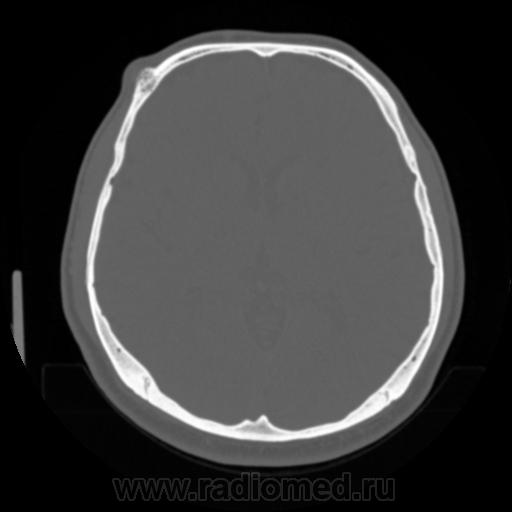

Предлагаю для обсуждения интересное исследование: мужчина уже 5 лет живет с данной патологией, которая несет только косметические дефекты.

Данный "рог" ему не мешает, но возможно данное обстоятельство служило поводом к разводу с женой

остеома это, жена не при чем, наверное

Однако, чёткого кортикального слоя нет. А нет ли спикул?

Думаю, что остеохондрома. Учитывая симптом сдавления внутренней пластинки и разрушение внешней-нельзя исключить миеломную. Недавно был такой же случай-больная решила тоже "рог" на лбу убрать, хирург едва не провалился в черепную коробку. При дообследовании-миеломная болезнь.

Думаю это гемангиома. Небольшое вздутие, звездчато-ячеистая структура. Точно не миелома.